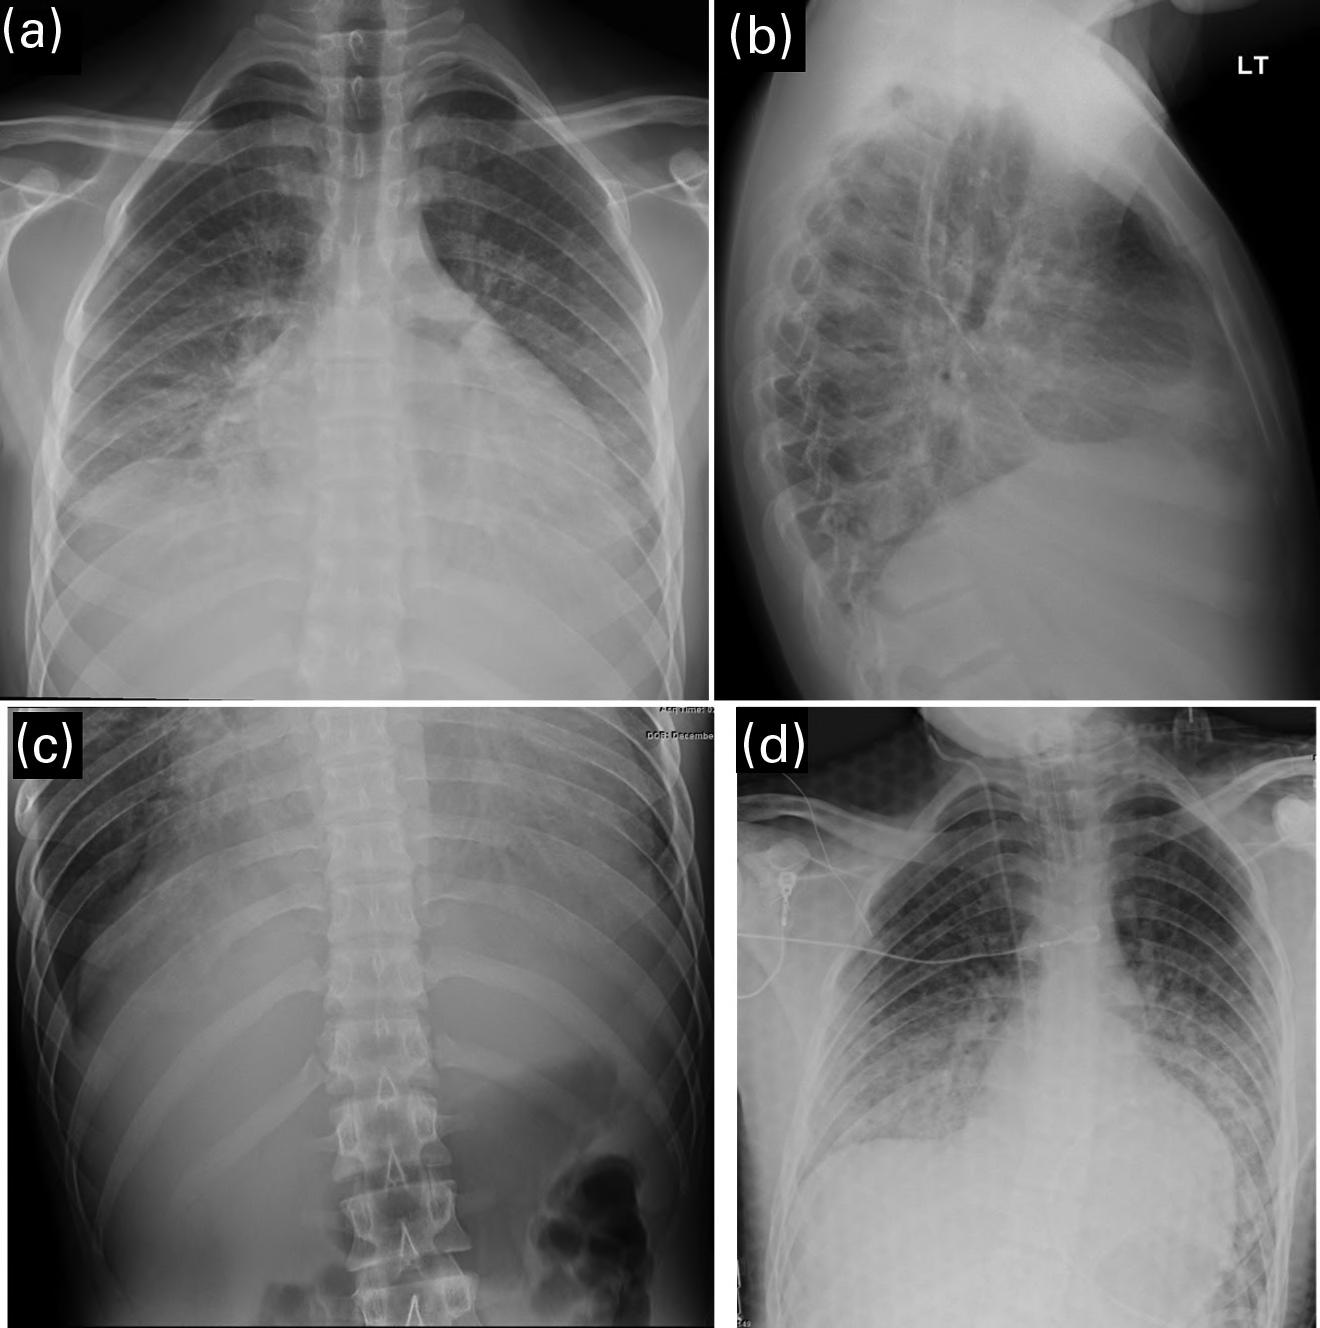

The clinicians for this patient started with a chest radiograph. The initial chest radiographic identified small pleural effusions and interlobular septal thickening, which were suggestive of interstitial pulmonary edema (see Figures 1.1a and 1.1b). Findings become more apparent when compared with a normal 16-year-old’s chest radiographs (Figures 1.2a and 1.2b). Because of the patient’s vomiting, an abdominal film was also obtained, which demonstrated significant cardiomegaly (see Figure 1.1c), thus leading to the diagnosis of dilated cardiomyopathy and/or pericardial effusion. On the chest radiograph, the reduced lung volumes and elevated hemidiaphragms masked the cardiomegaly, which was more apparent on the better penetrated abdominal radiograph.

FIGURES 1.1 a, 1.1b, 1.1c, AND 1.1d . (a, b) PA and lateral views of the chest demonstrating low lung volumes, pulmonary vascular congestion, interstitial opacities in the lung bases, and bilateral trace pleural fluid; (c) the abdominal radiograph is better penetrated than the chest radiograph, and shows an enlarged cardiac silhouette; and (d) post-procedure chest radiograph showing decreased size of the cardiac silhouette after drainage of the pericardial effusion.

Other tests that may help facilitate a timely diagnosis include a bedside ultrasound (US) for anatomic and functional evaluation, as well as assessment for pericardial fluid. This patient had an echocardiogram that showed a pericardial effusion, which was subsequently drained. A repeat chest radiograph shows the heart following the procedure (see Figure 1.1d).

FIGURE 2.1. AP view of the chest demonstrates bilateral diffuse pulmonary air space opacification.

2.2. A normal neonatal chest radiograph. Note the sharp costophrenic angles (small white arrows), the aerated lung extending below the level of the 6th rib anteriorly (long white arrow), and the contour of a normal for age thymus expanding the superior mediastinum (small black arrows).

CXR reflects the underlying pathophysiology, retained fetal lung fluid. This is seen in Figure 2.3 with interstitial opacities ( thickening of the fissures and streaky opacities radiating from the hila), normal to increased lung volumes, and possibly small volume pleural fluid. A “prominent” cardiothymic silhouette may also be present. Blood gas measurements may

FIGURE 2.3. Neonatal chest radiograph with interstitial opacities and fissural thickening with normal to increase lung volumes suggestive of TTN.

CXR reflects the underlying alveolar instability due to abnormal surface tension, demonstrating ground-glass/granular opacities and air bronchograms, as seen in Figure 2.5. Low lung volumes were classically described, but most neonates undergo imaging while under positive pressure support, often resulting in hyperinflation on the radiograph. Pleural effusions are not typical and may be an important clue to the possibility